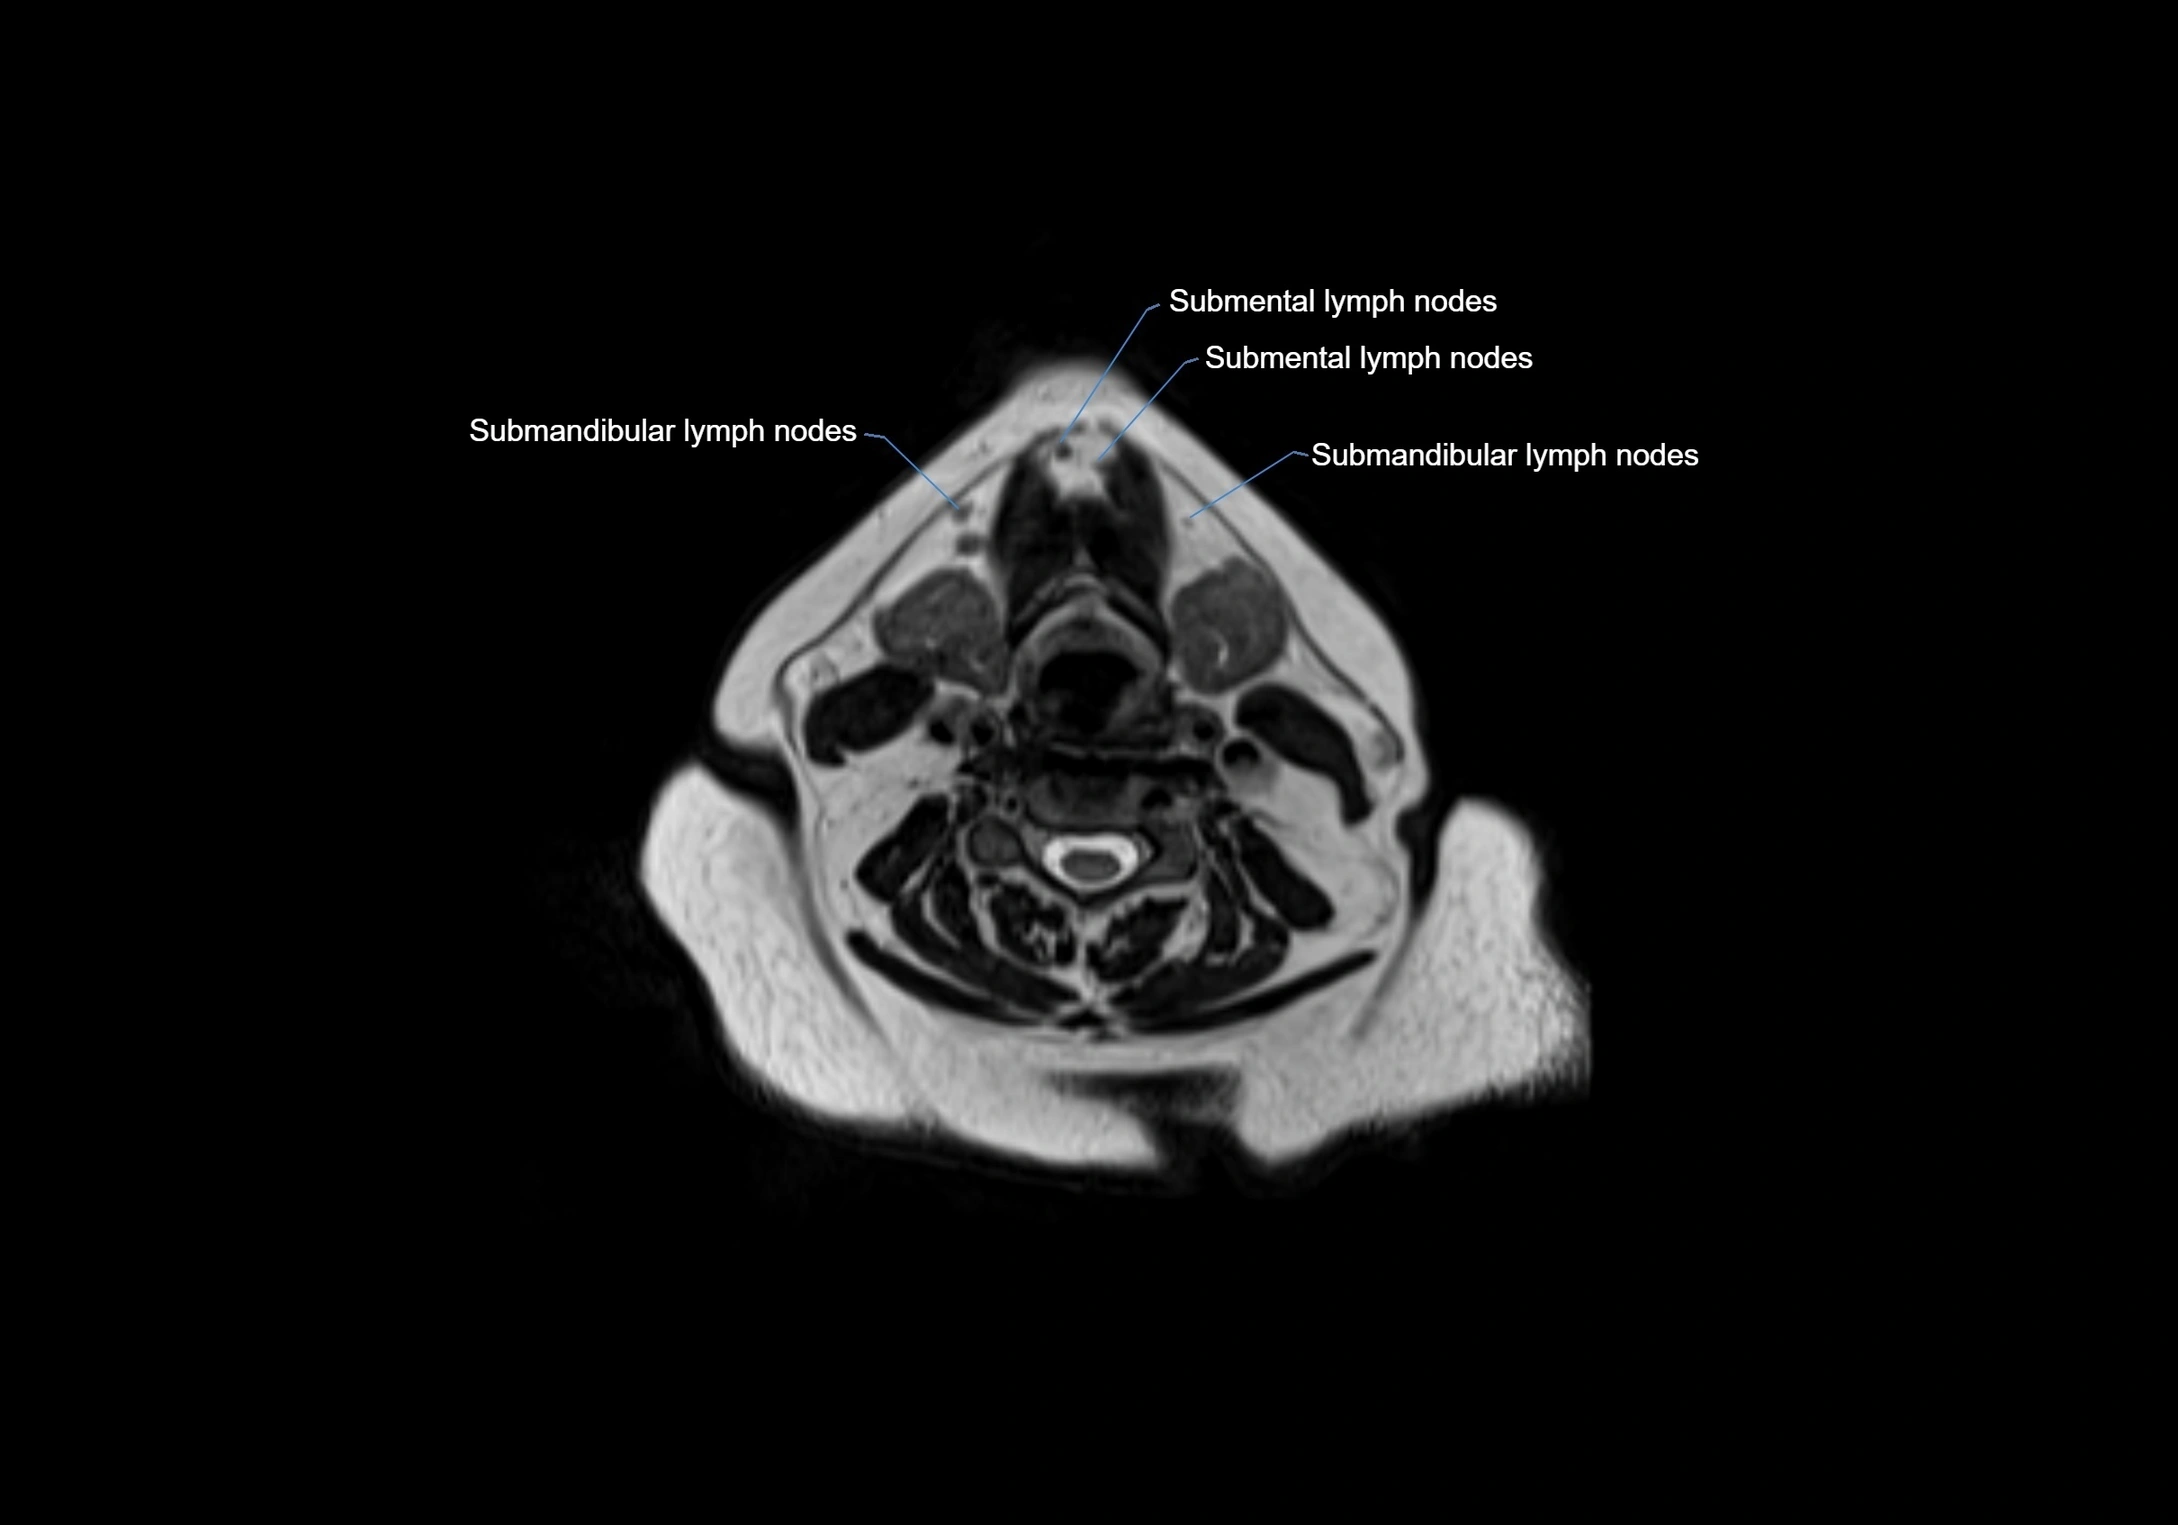

Accessory lymph nodes are small, secondary lymph nodes located along the main facial and cervical lymphatic chains, often adjacent to primary lymph nodes, such as preauricular, submandibular, or occipital nodes. They are typically less than 5 mm in diameter, embedded within subcutaneous fat or connective tissue, and may be variable in number and location. These nodes provide additional filtration and immune surveillance for lymph collected from the face, scalp, and neck regions. Accessory lymph nodes are usually non-palpable in healthy individuals but may enlarge in response to infection, inflammation, or metastasis, making them clinically significant.

Location

• Found along primary lymph node chains, including preauricular, submandibular, parotid, and occipital regions

• Embedded in subcutaneous fat or superficial fascia, often lateral or posterior to primary nodes

• Variable in number; may occur unilaterally or bilaterally, depending on individual anatomy

MRI Appearance

T1-weighted images:

• Normal accessory nodes appear as small, oval hypointense to intermediate signal structures within subcutaneous fat

• Surrounded by hyperintense fat, enhancing contrast for visualization

• Pathological nodes may appear enlarged or rounded, sometimes with cortical thickening